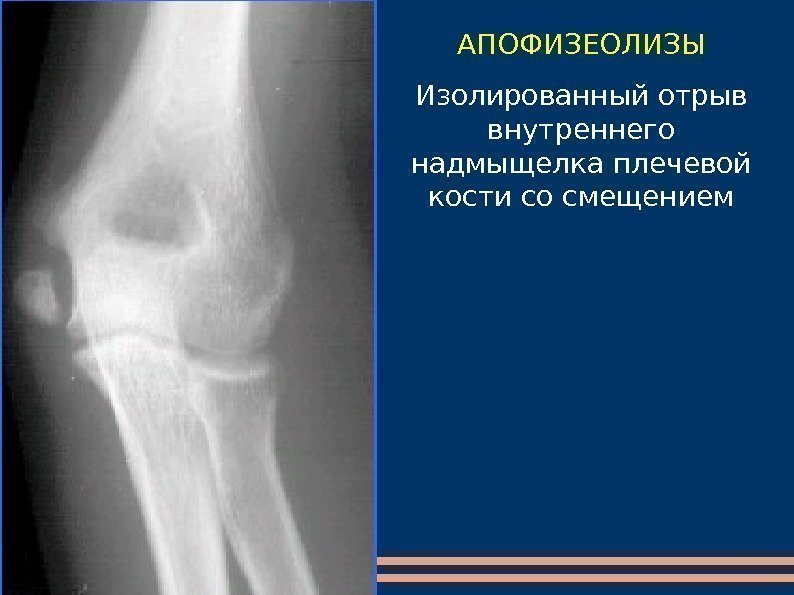

АПОФИЗЕОЛИЗЫ Изолированный отрыв внутреннего надмыщелка плечевой кости со смещением